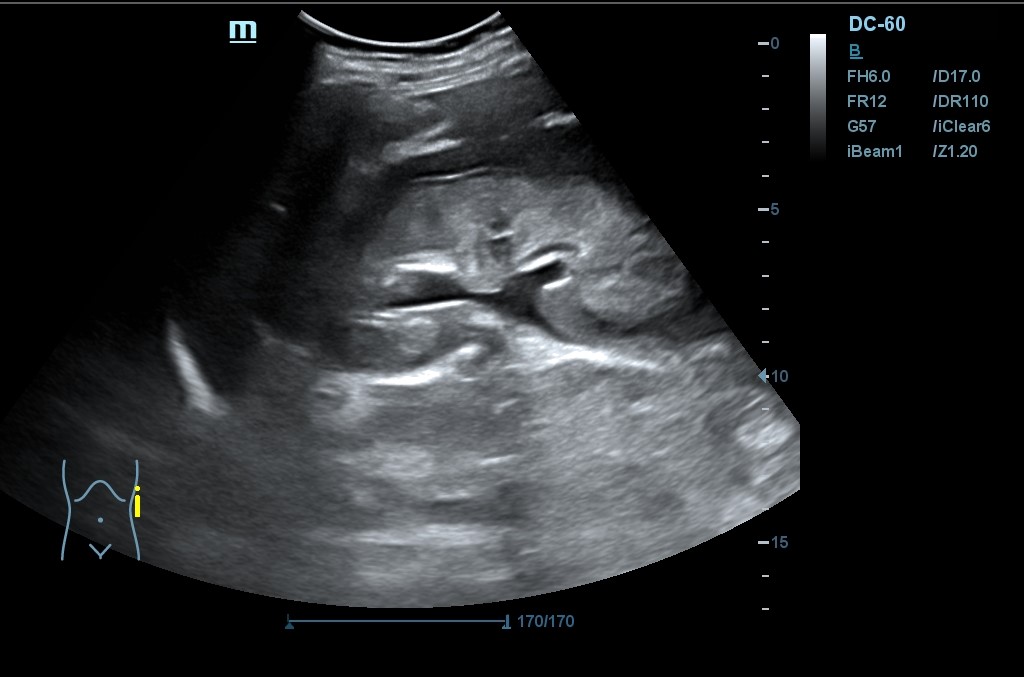

Hallazgo de lo que impresiona de nefromegalia izquierda de aproximadamente 14 cm con hidronefrosis bilateral grado 2.

Tras la segunda ecografía se deriva a la paciente a la Unidad de Diagnóstico Rápido de Medicina Interna donde ingresa para completar estudio. Tras ecografía en la que informan de extenso tejido hipoecoico periaórtico y perirrenal izq. (nefromegalia izq.) con extensión nodular al mesenterio, se establece la sospecha de síndrome linfoproliferativo, así como en un TC posterior y que se confirma como Linfoma No Hodgkin mediante biopsia.